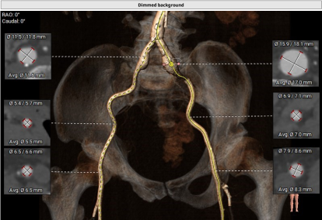

经外周血管入路评估

● 严重脊柱侧弯,外周血管条件差,严重横位心,经股入路难度高;